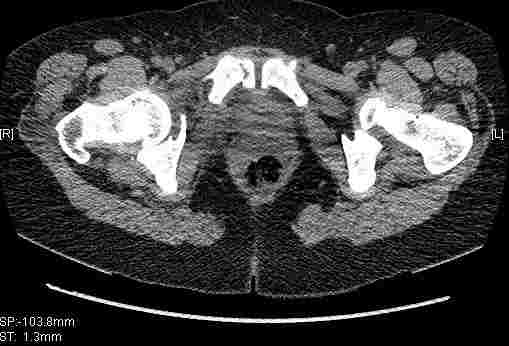

Удалось сегодня вывести пациентку в соседнюю больницу, где есть кт. Срезы сделаны только горизонтальные.

Приветствую,Антон.Рункова рядом нет,но после полученных данных КТ,обсуждали совместно.Итог обсуждения-развернутый ответ дать не получится,т.к.срезы выбраны не информативные.Если ориентироваться на данные 3D,то ,ИМХО,можно лечить на вытяжении.

Спасибо, Салават и коллеги. Насколько я понял,нужны срезы в сагитальной и фронтальной плоскостях?